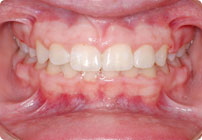

Galería

Masculino

Antes

Despues

Caso: 11 años

Adolescente: Clase II

Mordida Cruzada Posterior

Sin extracción

Sin uso de expansores

6 alambres superiores

5 alambres inferiores

Sin uso de elásticos

Retenedores: Interior Fijo de TMA y Hawley en superior

Tiempo de tratamiento: 14 Visitas